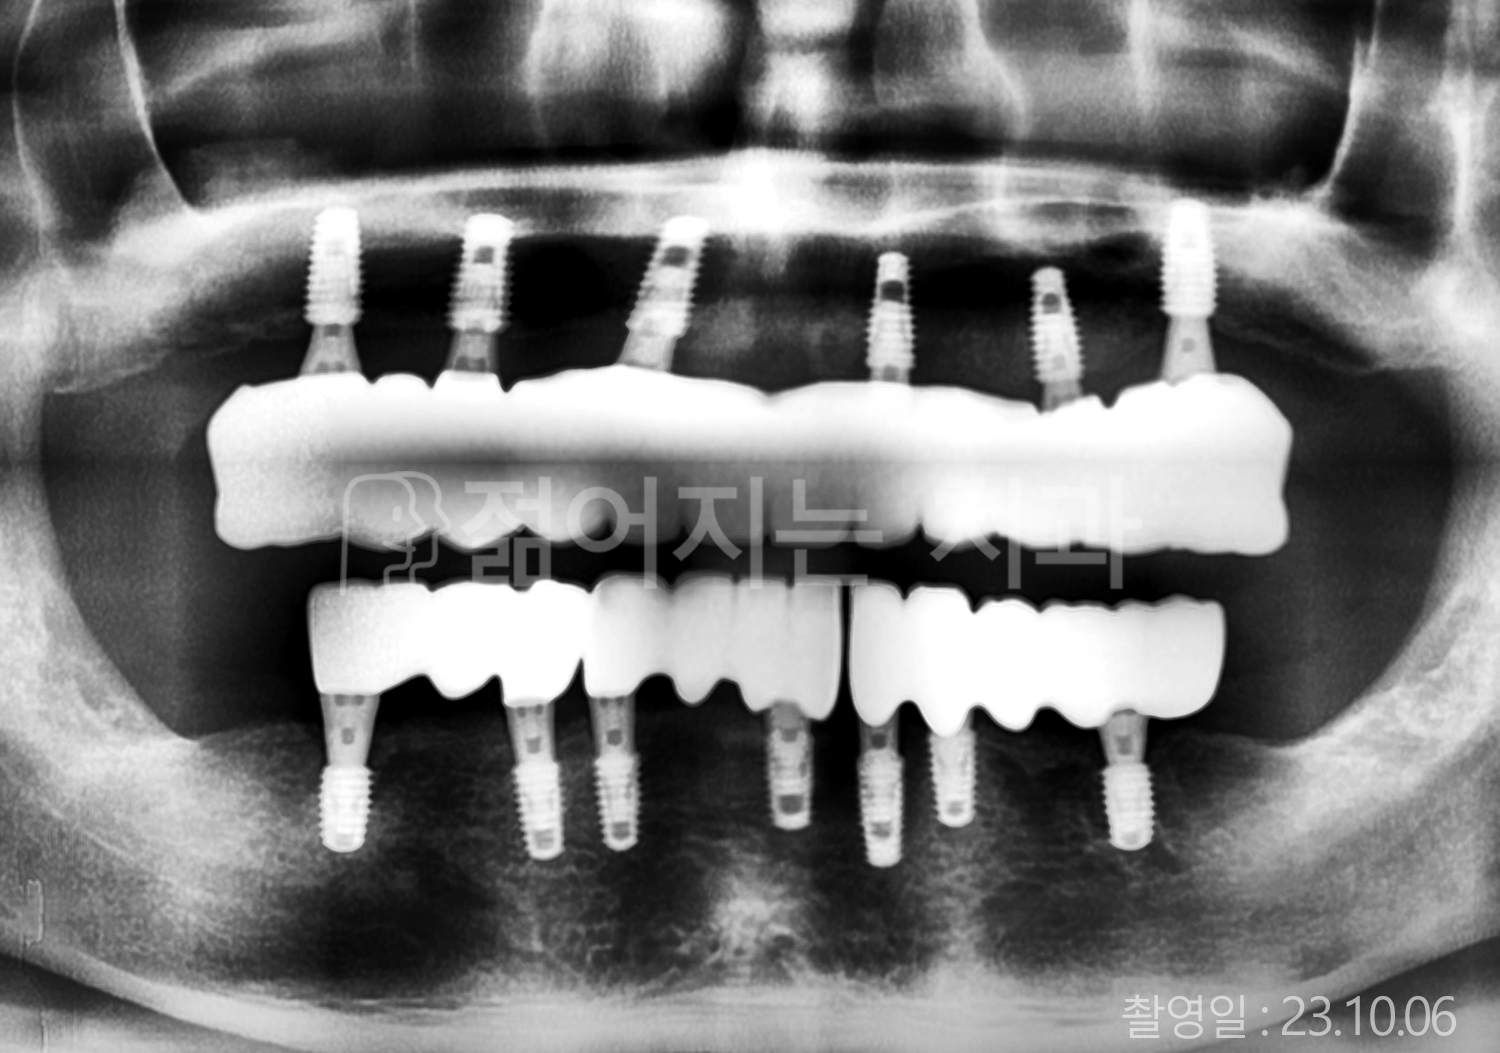

• 50대 전체치아 10개 이상 임플란트